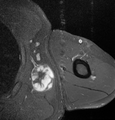

Medical imaging

Medical ultrasonography and magnetic resonance imaging (MRI) of liposarcomas are helpful and often essential in determining their extent, surgical accessibility, and relationship to any observed organ dysfunctions. Since ultrasonography is usually unable to distinguish a liposarcoma from a benign lipoma, MRI is the initial imaging of choice to provide evidence relative to making this distinction.[67]

In myxoid liposarcoma, it shows low signal intensity mass with high signal intensity foci on T1-weighted MRI images. The mass shows high signal intensity on T2-weighted images. This is because it contains predominantly mucoid substance (accounts for low signal intensity on T1) and small amount of mature fat (accounts for high signal intensity on T1).[68] The mass is well-defined, lobulated, multiloculated, or oval in shape without any infiltration into surrounding structures.[68]